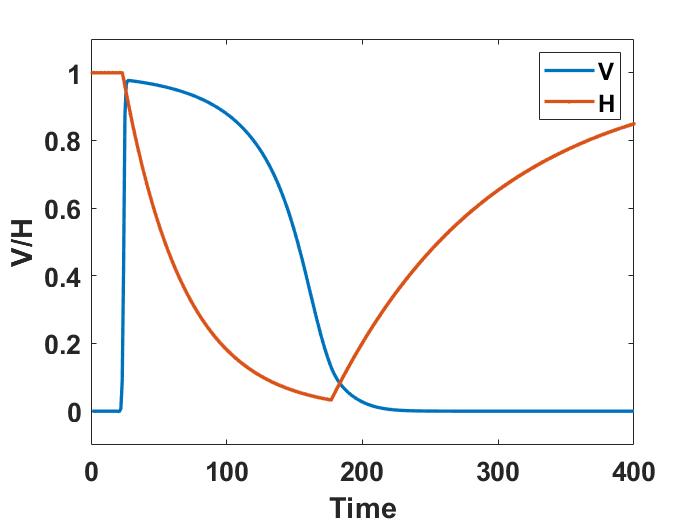

shown in Figure 7(b). Here, denotes the Heavisade function, the time when the stimulus ends, the position where the stimulus is applied, and its spatial width.

We use the same method that in the previous example for temporal integration. The solution shows the propagation of the electric excitation along the membrane. For instance, Figure 7 (c) shows the transmembrane current 50 ms after the stimulus ends. The tissue goes from a resting to an excited state. Finally, the membrane returns to the resting state awaiting for the next stimulus. This behavior can be observed in Figure 7 (d), where we show the evolution with time of the transmembrane voltage and the gate variable at the point in Figure 7 (c). As we can see, the cardiac tissue experiences the different stages of a heartbeat corresponding to those shown in [25].